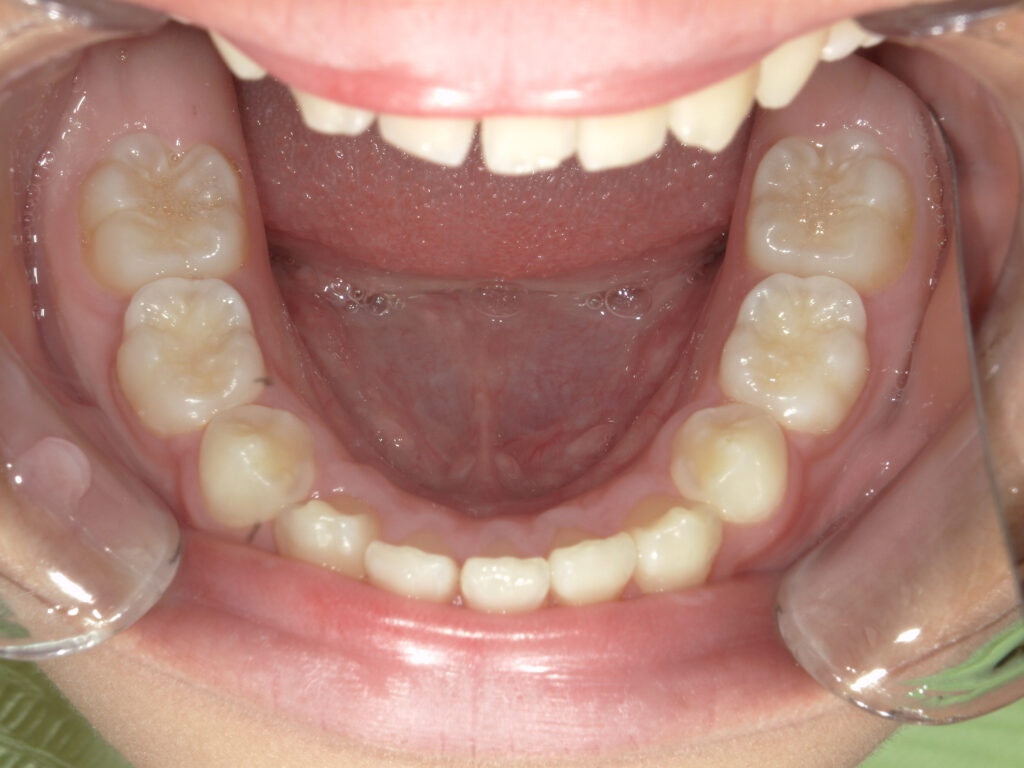

上顎

治療前

治療後

保定中経過(1年後)

下顎